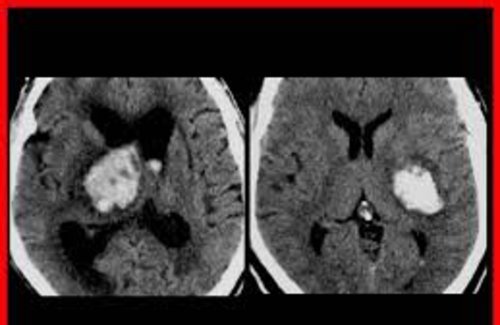

El diagnóstico de ACV es clínico - tomográfico, pudiendo ser según su naturaleza isquémicos (80%) o hemorrágicos (20%).

Los ACV hemorrágicos o hematomas se definen por la presencia de sangre en el parénquima cerebral.